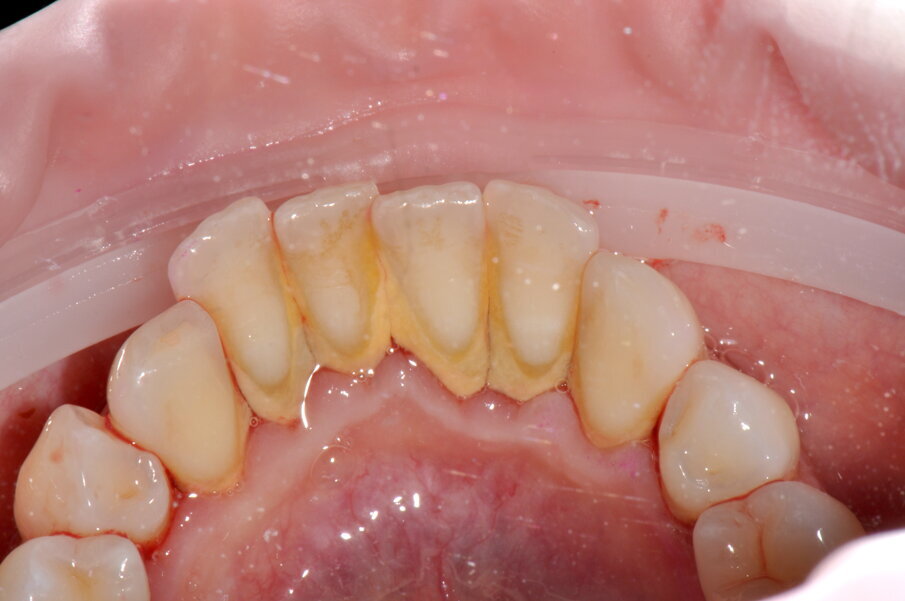

All’esame orale si evidenziano depositi di tartaro, in particolare nel quinto sestante nella zona linguale, e depositi di placca generalizzati (IP=2). I sondaggi parodontali risultano essere fisiologici con presenza di sanguinamento marginale e al sondaggio.

- Debridement meccanico con strumentazione piezoelettrica No-Pain® che rispetta i tessuti dentali grazie ai movimenti lineari e al controllo automatico della potenza emessa in base alla resistenza incontrata, con livello di potenza 50% e di irrigazione 100%, solo nelle zone in cui il tartaro è presente fino a sua completa rimozione (3a-4f);

Figg. 2a-2c - Foto scattate dopo l’utilizzo del manipolo sopra-gengivale, nelle aree vestibolare (2a), palatale (2b) e linguale (2c), senza la detartrasi con strumento piezoelettrico.